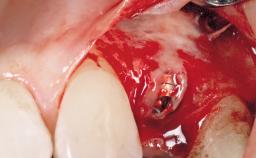

Immediate Flapless Placement of an Implant in a Maxillary Right Lateral Incisor Site

This 43-year-old male patient, a non-smoker, came to our practice because of a fracture of tooth 12 caused by a bicycle accident. Due to the combined para- and infrabony crown and root fracture, tooth extraction, and subsequent implant placement were suggested to the patient as the therapy of choice. The patient had high esthetic expectations with regard to the treatment outcome and asked for an immediate fixed provisional restoration. His individual esthetic risk profile summed up to a medium esthetic risk.

| Placement Protocol | Immediate implant placement |

| Tooth Site | Maxillary incisor or canine |

| Socket Morphology | Single-root socket |

| Socket Integrity | Sufficient, with intact bone walls |